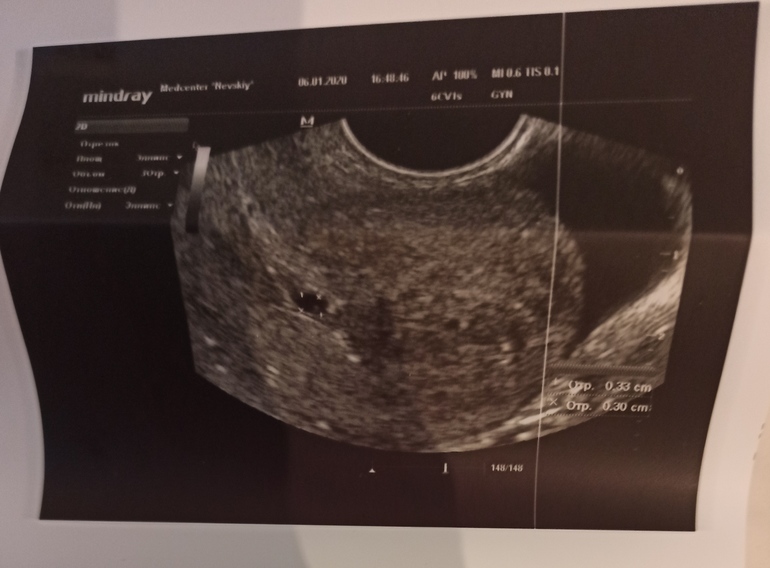

06.01.2020

Вот УЗИ от 27 декабря

, где яйцо деформировано, с отслойками и сгустками, в заключении написано вот:

И вот сегодня пошла снова на УЗИ, чтобы убедиться в том, что всё вышло. Но на УЗИ нет ни сгустков, ни отслоек, внутри обычная беременность малого срока, обычный эндометрий, яйцо не деформировано, что прикреплено хорошо. И сказала узист, что если бы я не показала предыдущее УЗИ и не рассказала про выделения, то она бы была уверена, что эта беременность нормальная.

И узист и врач склоняются к мнению, что это другое ПЯ, что было два зачатия(второе позже) и первое ПЯ вышло.

Но вроде расположение ПЯ на первом на втором снимках разное. Похоже, что это действительно два разных.

Тем более это ПЯ хорошее, ровненькое, видно, что там либо зачаток эмбриона, либо желточный мешочек. Матка в адеквате, без сугустов и прочего лишнего, в отличие от прового узи, там прям видно, что она вся в сгустках.

У вас в заключении не правильно указан размер ПЯ, на снимке плодное 3,3мм×3мм! А не 3,5см как указано в заключении! У вас очень маленький срок и красивое плодное яичко без деформации! Вполне может быть благополусгая беременность! 🙏🙏🙏🙏🙏

И оно у вас не пустое, там точно есть желточный мешочек!